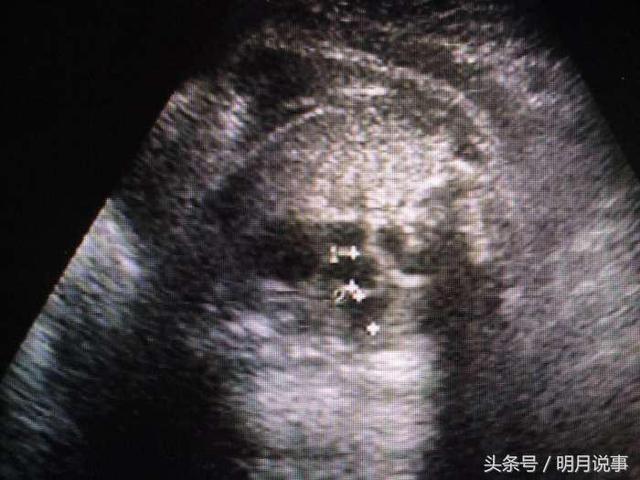

做第二次检查时,小陆是拖着软绵绵的进去的,流泪满面出来的。检查结果和第一次一模一样,胎儿心脏严重畸形,左心发育不良,永存动脉干。